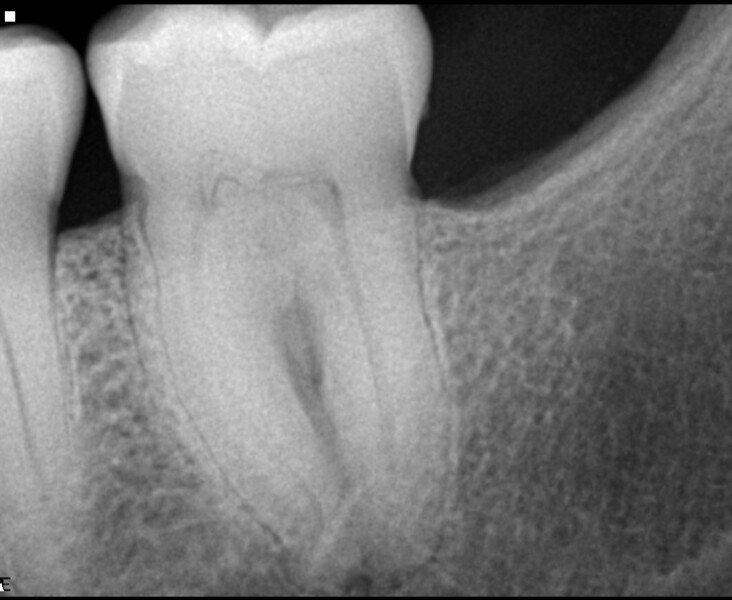

Using the endodontic mode in DTX Studio Clinic (Fig. 9), each slide and cut were examined, searching for the reason for the fistula of the mandibular molar. A possible cause of the fistula may have been the complex of lateral canals seen in the coronal part of the distal root (Fig. 10). Root canal therapy was initiated using the Traverse and ZenFlex files in the same sequence as that used for Case 1, and 3D obturation with elements IC was performed (Fig. 11).

Case 3